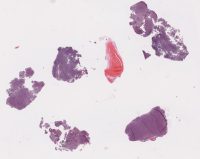

CANP2008-10.svs

40000 x 31663

@ 20X